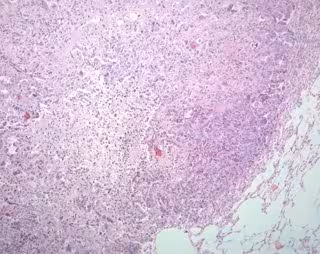

El de pulmón es la principal causa de mortalidad por cáncer en todo el mundo. La evolución del paciente está estrechamente vinculada a la etapa del tumor en el momento del diagnóstico. Por desgracia, la mayoría de los pacientes son diagnosticados en etapas tardías, cuando el tratamiento curativo ya no es posible.

Actualmente, la citología es el método estándar para el diagnóstico de este tipo de cáncer en muestras respiratorias mínimamente invasivas, pero es un método con baja sensibilidad. Por ello, los investigadores se propusieron identificar biomarcadores epigenéticos con utilidad clínica para el diagnóstico de cáncer, con el objetivo de mejorar la precisión de las tecnologías actuales.